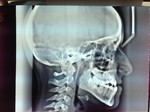

Paziente candidato a intervento di chirurgia Ortognatica